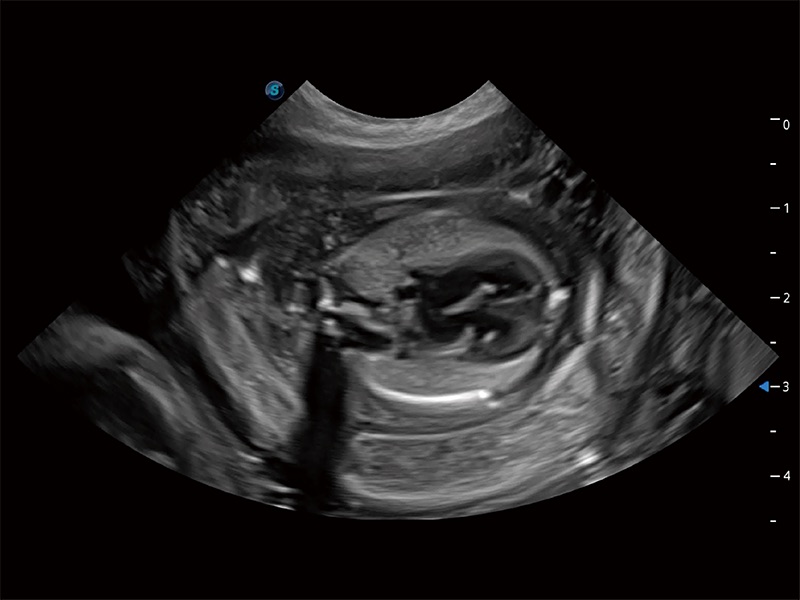

高性能和先进的临床应用工具可以为动物医生提供临床信心。ProPet 80 搭载了先进的腹部和浅表应用工具,帮助医生在日常临床实践中发挥前所未有的作用。

ProPet 80 专为动物医生设计,对不同的动物体型和生理结构作出了针对性的优化。通过动物影像专用软件,可满足个性化的应用需求,帮助动物医生获得更精确的诊断数据。

ProPet 80 全新的动物超声智能软件和丰富的探头群,为动物医生提供了高清晰度和精细分辨率的图像,无论在宠物、马科、畜牧还是实验室动物等应用中都可以轻松应对,为您的日常工作带来满意的体验。